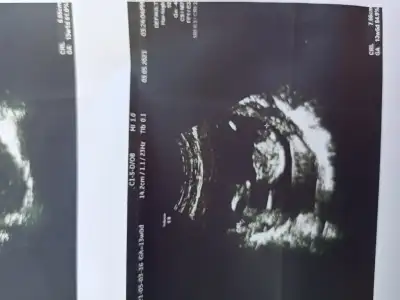

Kız sanki emin olamadım başka USG varsa paylaşınMerhabaIkra meyra 'cım. Benim de 12+4 ultrason görüntüm. Bize de tahmin de bulunabilirsen çok mutlu olurum

Kız sanki emin olamadım başka USG varsa paylaşın